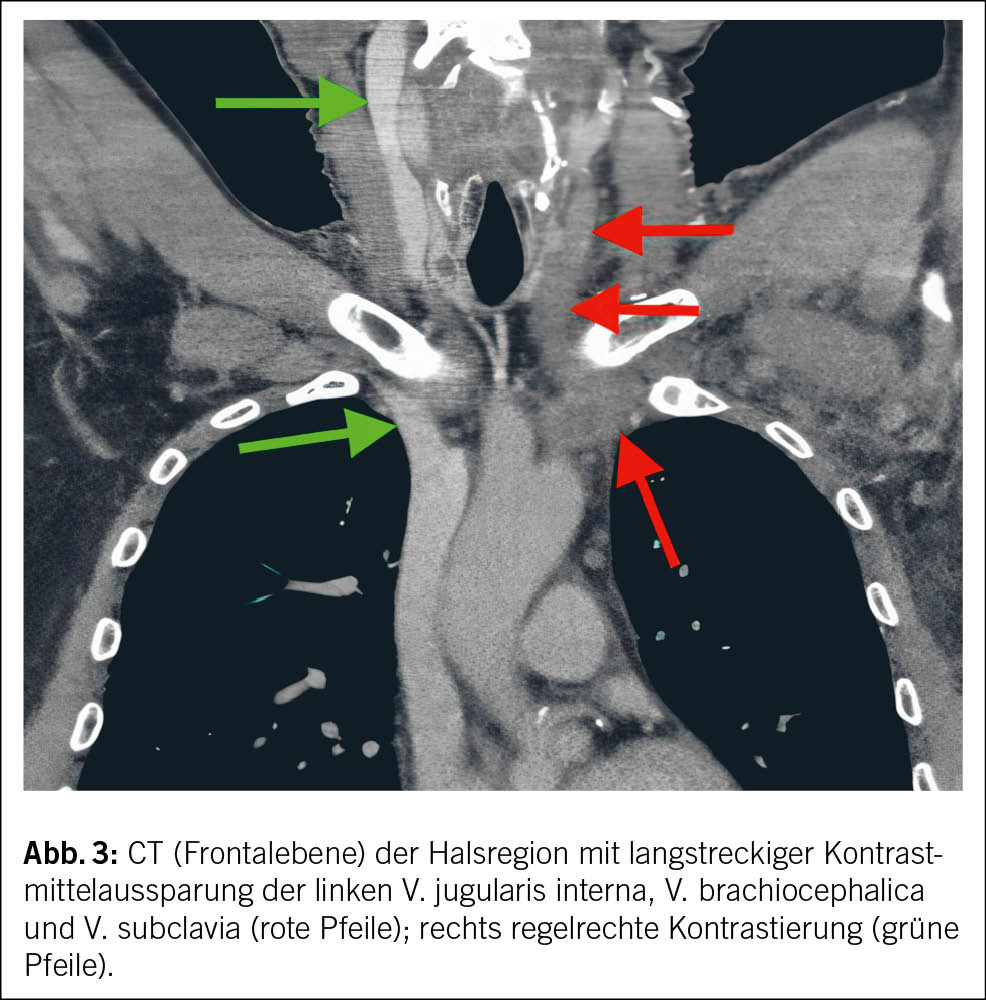

Aufgrund des Verdachts auf eine TVT der Vena jugularis erfolgte eine CT-Bildgebung der Hals- und Thoraxregion mit venöser Kontrastmittelphase. Die CT-Untersuchung bestätigte die Diagnose einer Thrombose im distalen Abschnitt der V. jugularis interna links. Zusätzlich wurde eine TVT der V. subclavia links, der V. axillaris links sowie der V. brachiocephalica links nachgewiesen, ohne Anhaltspunkte einer externen Kompression (Abb. 2 und Abb. 3).